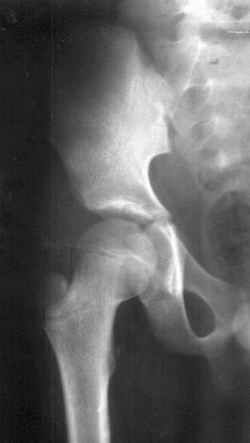

![Figure 3. X-ray Pelvis and femur in a two and a half year old male [102 kb]](others/ug_pics/3lr.jpg) |

Figure 3. X-ray Pelvis and femur in a two and a half year old male (Click to enlarge).

The case shown in figure 3 was a male, who was brought to the author for alleged sodomy on him. The police wanted to know his age, as a tender age could lead to stricter punishment to the accused. If we look at the X-ray carefully, we see that the head of femur has appeared. This meant that the age was above 1 year. But the greater trochanter has not yet appeared which allowed us to say that he was below 4 years. The actual age of the boy was found to be 2 and a half years from other evidences.